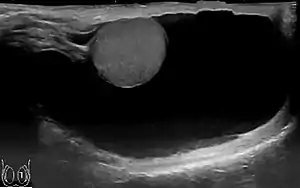

A hydrocele testis is an accumulation of clear fluid within the cavum vaginale, the potential space between the layers of the tunica vaginalis of the testicle. It is the most common form of hydrocele and is often referred to simply as a "hydrocele". A primary hydrocele testis causes a painless enlargement in the scrotum on the affected side and is thought to be due to the defective absorption of fluid secreted between the two layers of the tunica vaginalis (investing membrane). A secondary hydrocele is secondary to either inflammation or a neoplasm in the testis.

A hydrocele testis feels like a small fluid-filled balloon inside the scrotum. It is smooth, and is mainly in front of the testis. Hydrocele testes vary greatly in size and are typically painless and harmless. However, as the fluid continues to accumulate and the scrotum further enlarges, more discomfort can be expected. Large hydroceles will cause discomfort because of their size. Sometimes pain can be in both testicles as pressure from the enlarged area puts pressure against the unaffected area which can cause discomfort to the normal testicle. It has also been found to decrease a man's sex drive and makes him less active for fear of enlarging the mass. As the fluid of a hydrocele testis is transparent, light shone through the hydrocelic region will be visible from the other side. This phenomenon is called transillumination.

Through diagnostic ultrasound the accumulation of fluids can be diagnosed correctly.